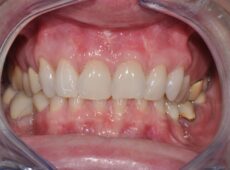

Estetica dentale

Un trattamento volto a migliorare l’estetica e l’armonia dei denti, delle gengive e del sorriso nel suo insieme con svariate tecniche come sbiancamento, ortodonzia, rimodellamento gengivale e faccette.